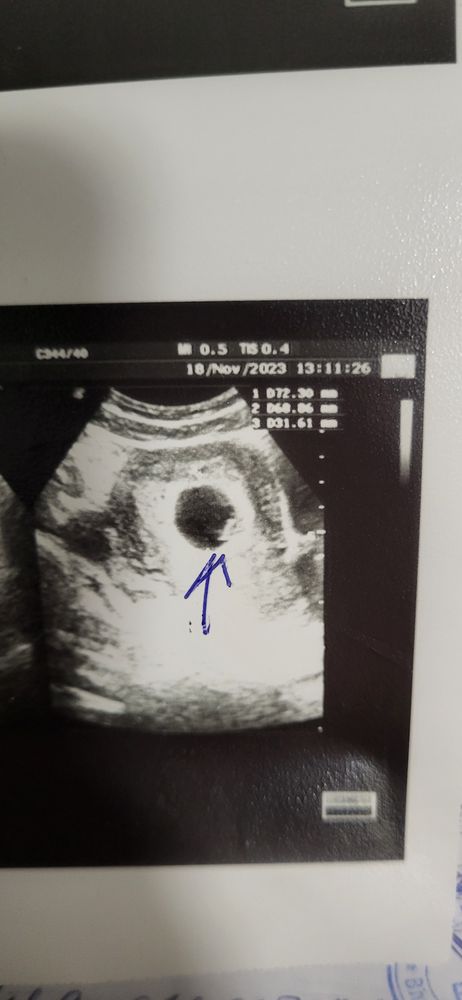

6.5 недель беременности, узи.

Сегодня ходила искать свою креветочку к своему любимому узисту. Последний раз делали трансвагинально 7.11 в больнице, ставили 4-5 недель. Думала мой узист тоже будет тем же способом смотреть, а он сказал, что нет, срок уже хороший, видно через живот будет и нечего лишний раз туда ползать. Посмотрели через живот. Нашли мою креветочку, срок 6.5 по узи) Сердцебиение показал на экране))) Это так мило. Сказал нормальная беременность, здоровая, хорошо закрепилась лялечка. Ни отслоек, ни гематом не нашёл. Обнаружил кисту в ля, сказал ничего с ней делать не надо, рассосётся. Вот думаю, недельку подожду и пойду вставать на учёт. Давайте погадаем по месту прикрепления, мальчик/девочка?)